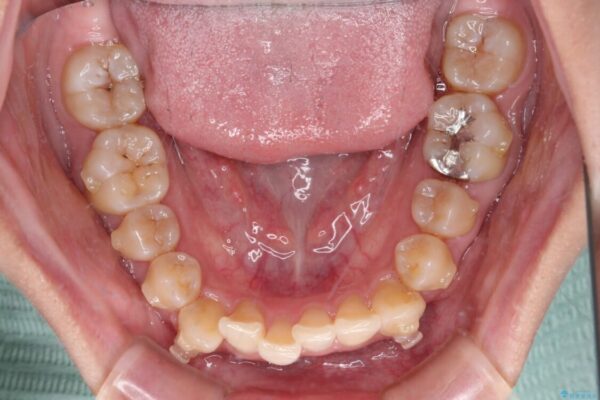

治療前、下顎前歯のデコボコが集中しており、奥歯の咬み合わせは、上顎に対して下顎が前方位にある状態でした。下顎の歯列を後方へ移動させる治療はインビザラインの得意とするところですので、1年程度で無事に治療を終えることができました。

治療後

• 【モニター】下顎前歯のデコボコをインビザラインできれいに 治療後画像